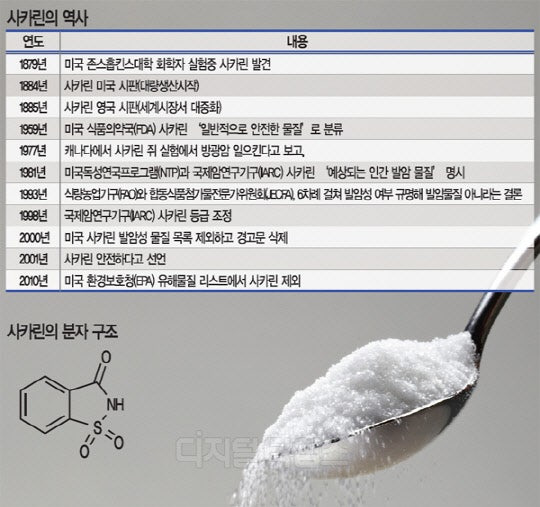

2. 사카린의 역사

사카린의 역사는 꽤 오래되었어요. 1879년, 미국의 화학자인 이그나츠 시겔이 발견한 이후, 20세기 초반에는 대량 생산이 가능해졌어요. 1970년대에는 사카린이 암을 유발할 수 있다는 논란이 있었지만, 이후 연구를 통해 안전성이 입증되었어요.